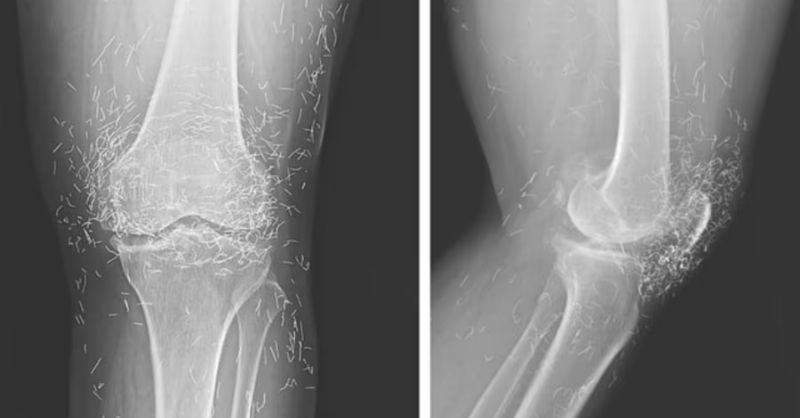

X-Ray Reveals Hundreds of Gold Needles in Woman’s Knees

Doctors in South Korea were astonished when they discovered that a 65-year-old woman’s knees were filled with hundreds of tiny gold acupuncture needles, apparently left there intentionally during...